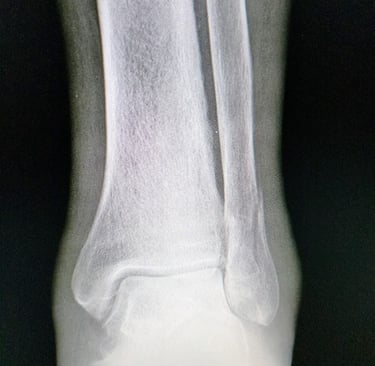

Radiografías: Permiten identificar el tipo y la ubicación exacta de la fractura.